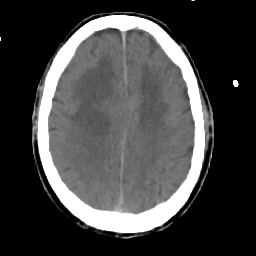

Meningioma: Roentgen-ray CT #2 -- Slice #14

[Home][Help][Clinical] Slice 14